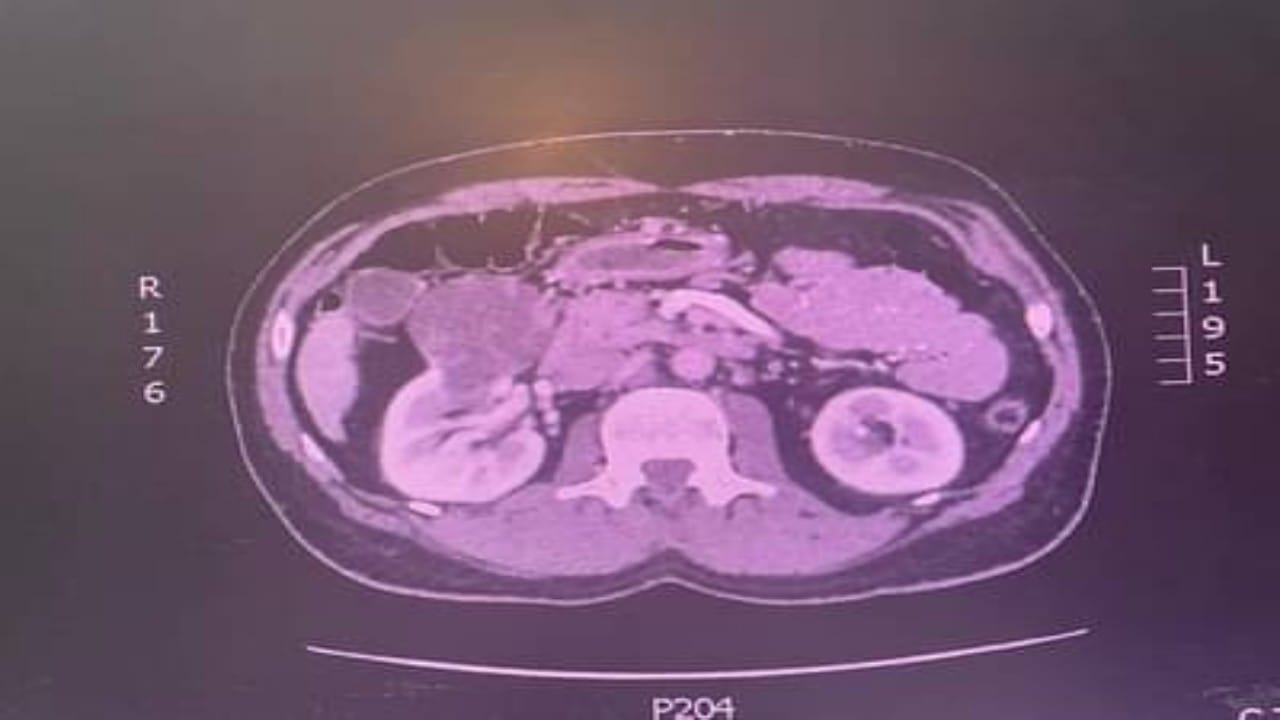

استئصال ورم كلوي لمريض خمسيني في الطائف

نجاح استئصال كيس دموي من كلية مريض في سكاكا